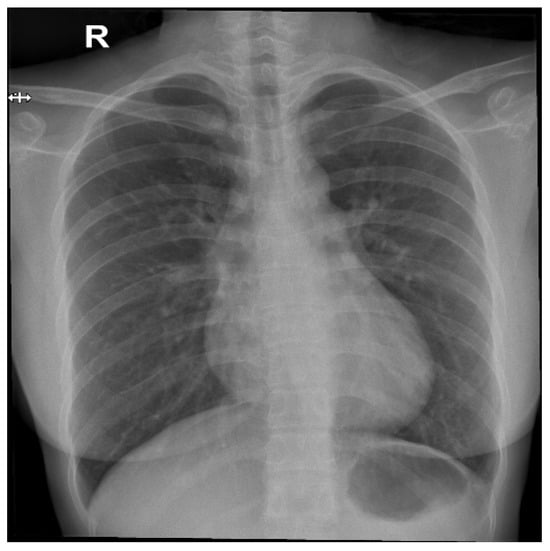

From a visual perspective, as illustrated in the comparison images above, both the RSCM as in Figure 1 and NIH as in Figure 2 datasets exhibit comparable quality in terms of resolution, clarity, and diagnostic relevance. This similarity ensures that image quality does not introduce any significant bias or variation.